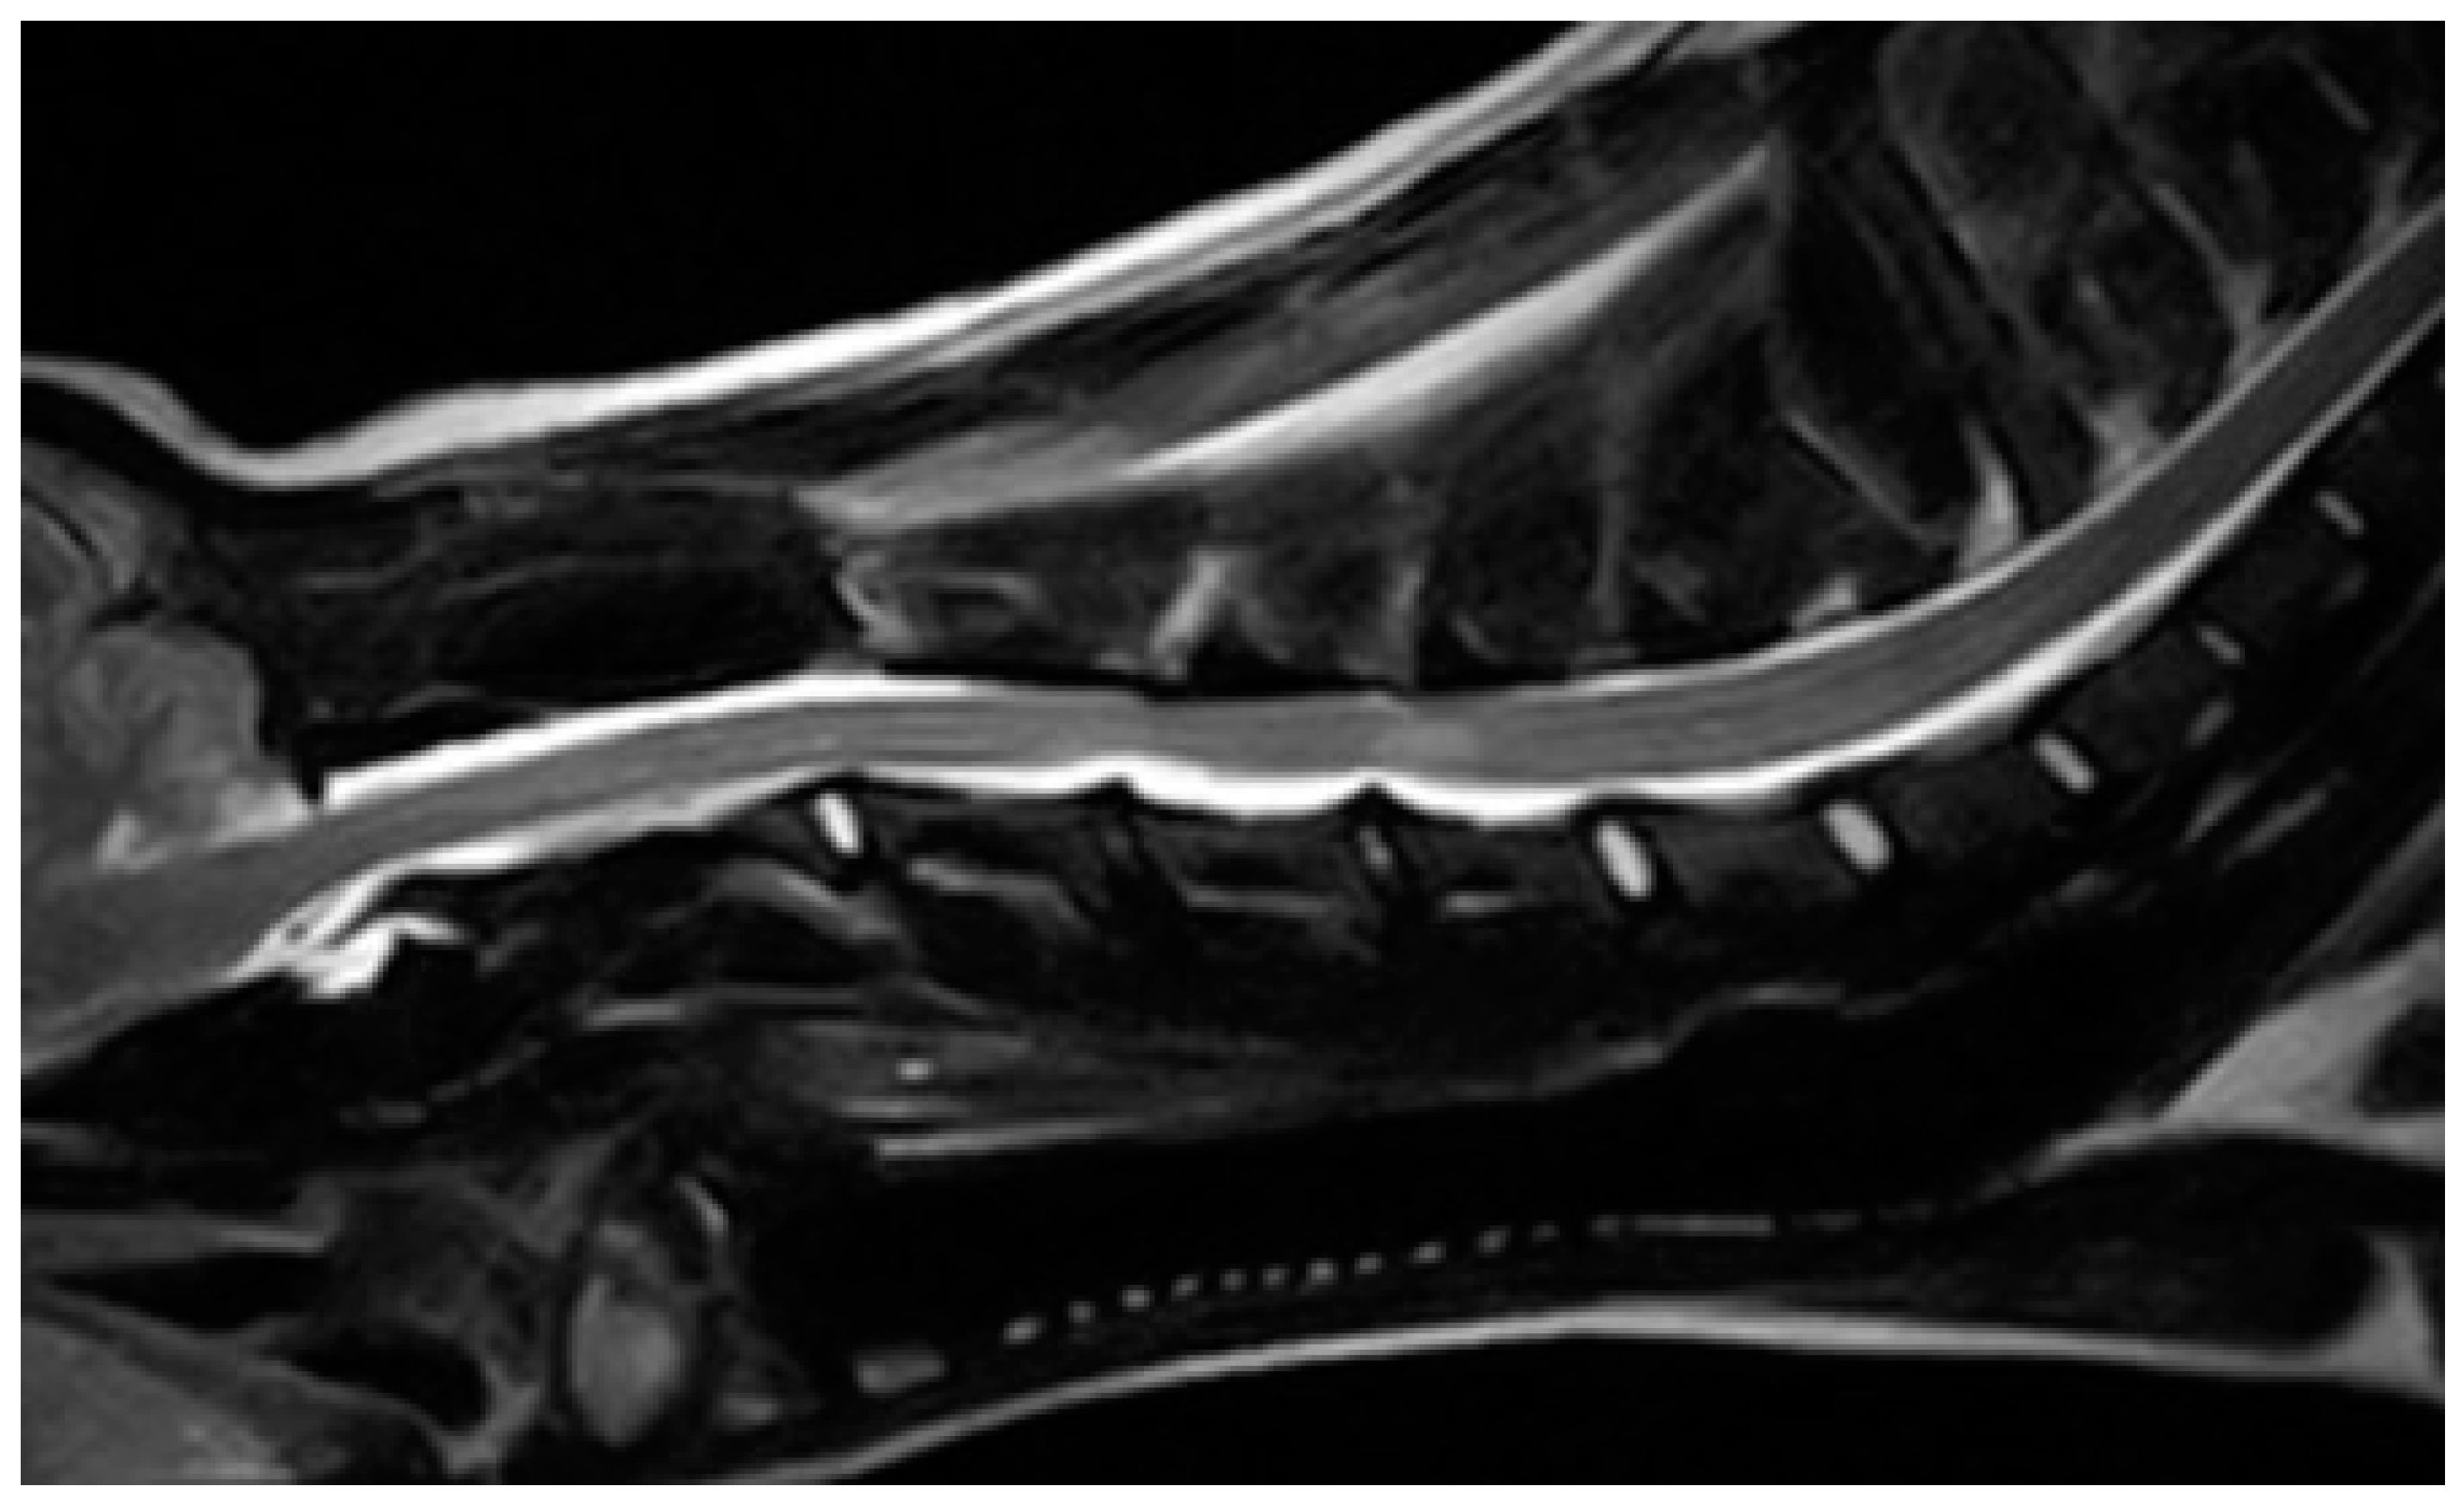

2. Case Description